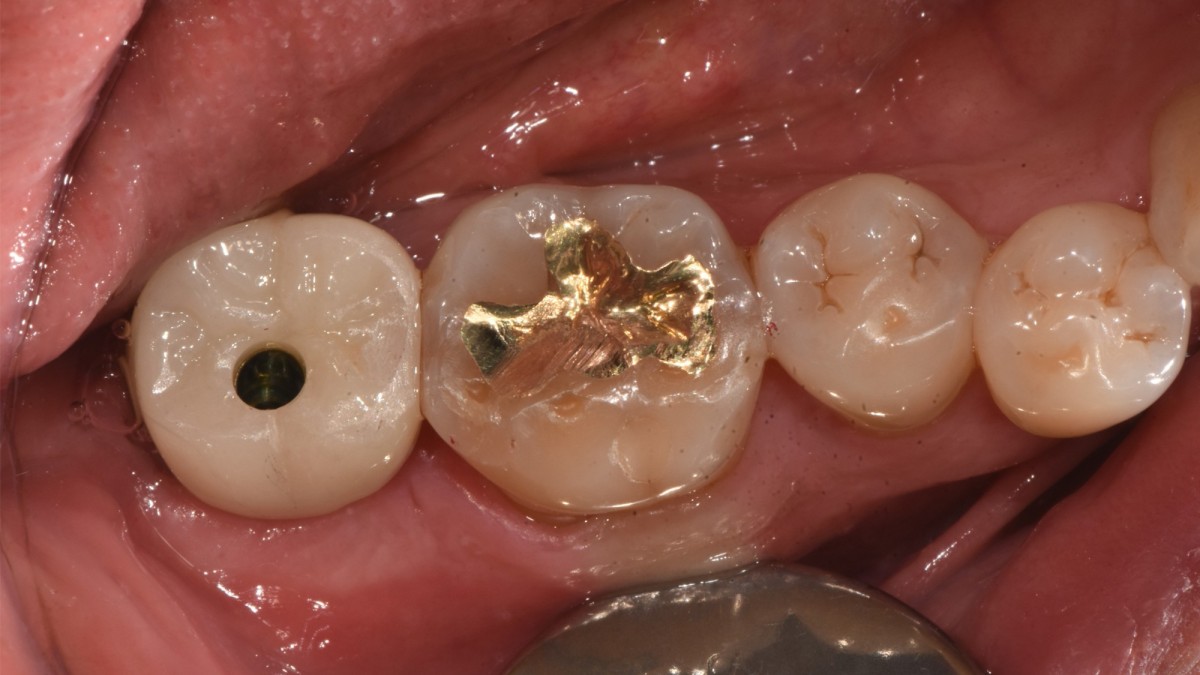

A 47-year-old male patient had a crown with an ill-fitting margin and crack-tooth syndrome in the lower 2nd molar. No systemic issue.